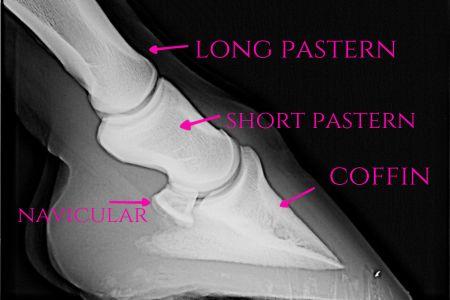

Bones of the hoof

The coffin bone

- The coffin bone has many other names, including the pedal bone, the third phalanx, the distal phalanx, and P3. It’s the last bone in the horse’s leg, just below the short pastern bone. It also cups the navicular bone, which sits nestled at the back end of the coffin bone and the short pastern, towards the heels.

- Laminae connect the bone to the hoof wall. The porous bone surface gives soft tissue anchors for attaching laminae, tendons, and the digital cushion.

- The coffin bone helps to anchor some tendons, protects blood vessels, protects nerves, and assists with the break over of the hoof.

- When looking at the coffin bone, the bottom edge supports the horse’s weight. The wing of the coffin bone is along the back, where the deep digital flexor tendon attaches.

- As a horse ages, the coffin bone can change shape and density, and may fracture.

The navicular bone

- The navicular bone, also known as the distal sesamoid bone, is a small, flattened bone tucked behind the coffin bone. It rests between the short pastern bone and the deep digital flexor tendon.

- This small bone helps stabilize the hoof and helps your horse move smoothly.

- The navicular bone is notorious for being associated with swelling, degeneration, and breaks. Navicular disease, commonly referred to as “navicular” describes damage to this bone and its surrounding structures. Navicular disease can be painful and may benefit from corrective shoeing and other supportive care. It’s often tricky to diagnose, as a horse often suffers from both front limbs affected, thus making a horse appear sound.

The short pastern bone

- The short pastern bone, or the second phalanx or P2 bone, sits above the coffin bone and is mainly outside the hoof. It’s cylindrical and, like the coffin bone, is the attachment for tendons and ligaments.

- This handy little bone plays a big role in shock absorption and transferring weight throughout the limb. Ringbone affects the short pastern bone, causing bony growths that may circle the joints around the bone. Horses can also develop arthritis in this area.

Here you can see the P1, P2, and P3 (top to bottom)